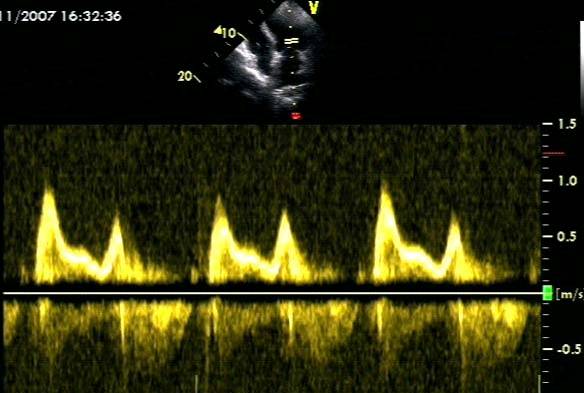

◆不典型的模式,如三相二尖瓣血流速度模式。

房 颤

◆TR > 2.8 m/s提示 LAP升高;

◆LVEF下降的患者,二尖瓣E峰DT≤160ms提示左室舒张压升高,临床预后较差;

◆ 其他提示有舒张功能障碍的指标:

①二尖瓣E峰加速度≥ 1900 cm/s2

② IVRT ≤65 ms

③肺静脉 D 波减速时间≤220 ms

④ E/Vp ≥1.4

⑤ E/e’≥11